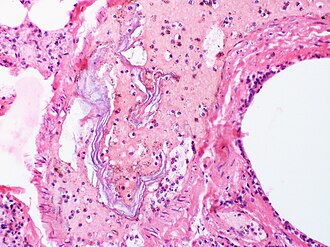

Točan način prijelaza plodne vode u krvotok majke nije jasan. Vjerojatno dolazi do nastanka pukotina amniona, pri čemu se plodna voda, uvlači između koriona i decidue pomoću kontrakcija maternice i utiskuje se u intervilozne prostore posteljice (krvotok majke). Prijelaz sastojaka plodne vode (kazeozni vreniks, mekonij, pločasti epitel, epidermis, sluz, lanugo dlačice) ima za posljedicu izraženu sklonost trombozi, jer se u plodnoj vodi nalazi trombokinaza i kalcij. Kao rezultat toga stvaraju se trombi u venama maternice, ali i u plućnim krvnim žilama majke [21][22][23][24][25].